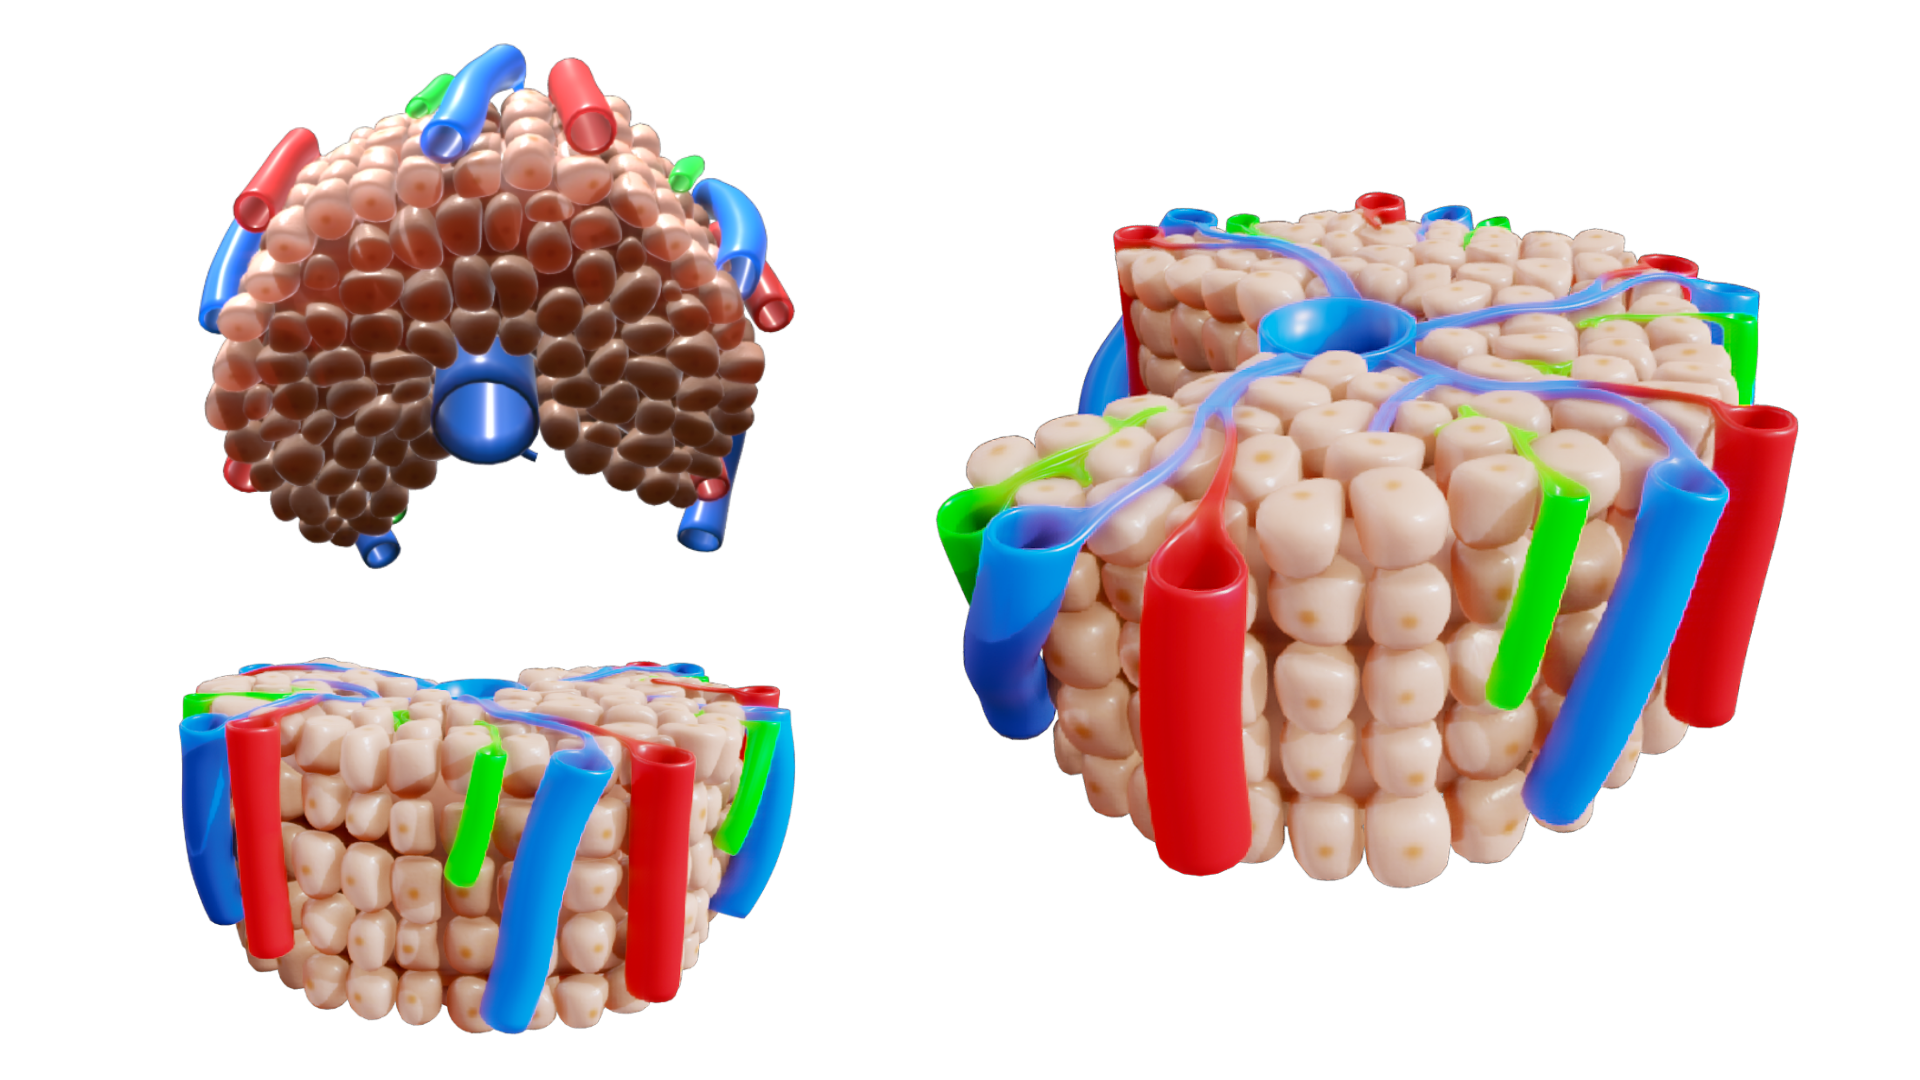

Структурная организация больших слюнных желез. Морфология секреторных отделов и системы выводных протоков. Печень: клеточные типы, характеристика классической печеночной дольки, портальной дольки и печеночного ацинуса. Кровоток и отток желчи. Морфология экзокринной части поджелудочной железы.